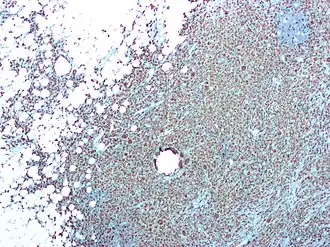

Acute pyelonefritis is een gelokaliseerde ontsteking van de nier en het nierbekken. Het nierparenchym vertoont abcessen, waarin pus: witte bloedcellen, bloedstolsels en –afbraakproducten, celresten en bacteriën opgeslagen zit. De nierbuisjes (tubuli) worden beschadigd door het exsudaat en kunnen afgietsels van witte bloedcellen bevatten, die in de urine kunnen worden teruggevonden als pijpvormige celklonteringen. In een vroeg stadium zijn de glomeruli en de vaatjes nog niet aangedaan. Chronische pyelonefritis kan leiden tot littekenvorming en fibrosis.